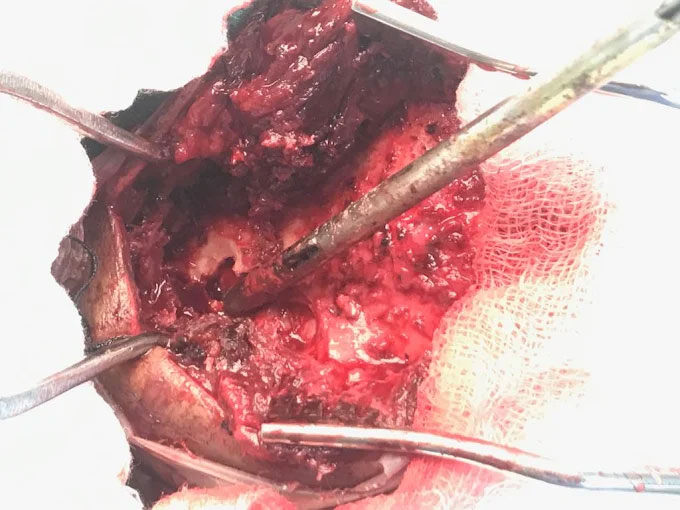

Surgical Highlights